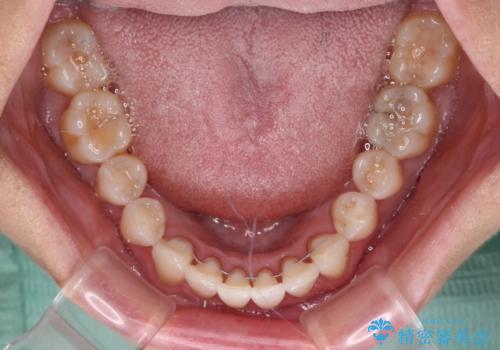

- 前歯の上下スペースによる食べにくさを気にして来院された患者様です。

インビザラインにより上下の前歯の隙間を閉じていくこととしました。

舌の突出癖があると上下前歯にスペースが開くため、矯正治療を機会に舌癖を改善するトレーニングを行ってもらい、矯正治療後の後戻りを防止するように指導しています。